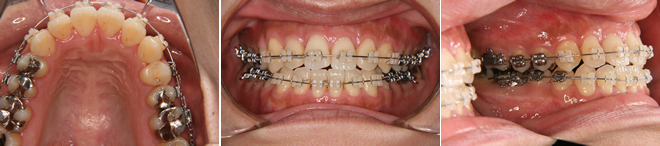

| 主訴 | 噛み合わせが逆、八重歯 |

| 年齢・性別 | 20歳 / 女性 |

| 治療方針 | オトガイの突出感が強く、顔貌改善には外科矯正が適応と考えられたが本人が希望しなかったため、マルチブラケット装置のみで治療を行った。 |

| 抜歯部位 | 上下顎左右小臼歯(計4本) 治療後に下顎左右第3大臼歯(親知らず) |

| 使用装置 | マルチブラケット装置 |

| 治療期間 | 27か月 |

| リテーナー | 上顎インビジブル、下顎スプリングリテーナー |

| 費用 | 825,000円(税別) |